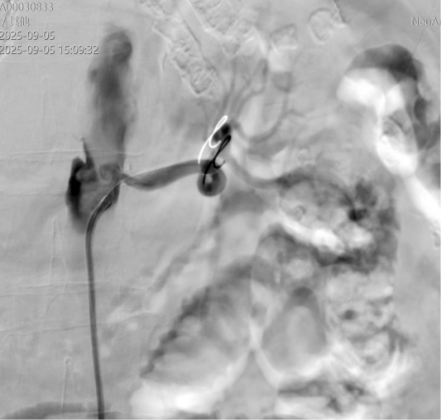

心血管团队与介入团队协同作战,为患者实施介入手术。手术中,医生采用微穿刺针成功穿刺双侧股总动脉并置入动脉鞘管,造影清晰显示右侧髂总动脉口部狭窄60%-70%、腹主动脉下段局部扩张,左侧髂总动脉近段呈线样重度狭窄(99%),左侧肾动脉口部重度狭窄(95%)。在高清影像引导下,团队精准操作,通过球囊逐级加压扩张后,于左侧肾动脉及左侧髂总动脉分别植入支架1枚,右侧髂动脉经球囊扩张后血流明显改善。手术成功开通狭窄血管,恢复了左侧肾脏及双侧髂动脉的正常血流。

(术中图片)